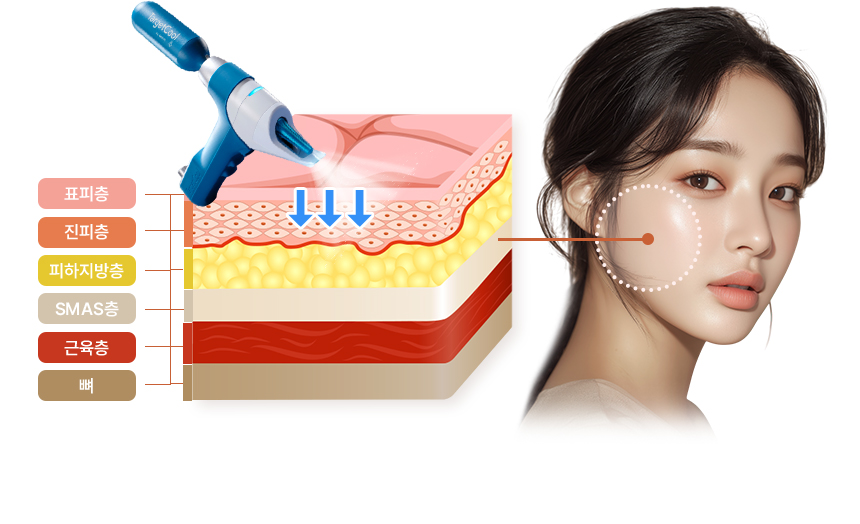

Chill하게~ 비침습 냉각 마취로

통증은 줄이고, 탄력은 높이다!

STEP 1

-10℃~-5℃ 냉각기술로

-10℃~-5℃ 냉각기술로

시술전 통증 최소화

STEP 3

피부속까지 바꾸는 탄력 & 광채효과

아이스 니들링으로 진피층까지 스킨부스터 앰플투입